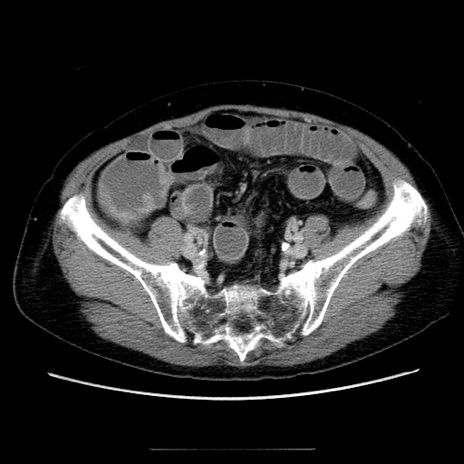

症例5(横断像)

【症例】70歳代女性

【主訴】お腹が張る

【現病歴】1週間くらい前から腹部膨満の自覚あり。昨日夜から増悪したため、本日救急外来受診。

【身体所見】意識清明、BT 36.5℃、BP 165/106mmHg、HR 80bpm、SpO2 98%、腹部:膨満、軟、自発痛・圧痛なし、触診にて不快感あり、腸蠕動音:減弱

【データ】WBC 12600、CRP 1.04